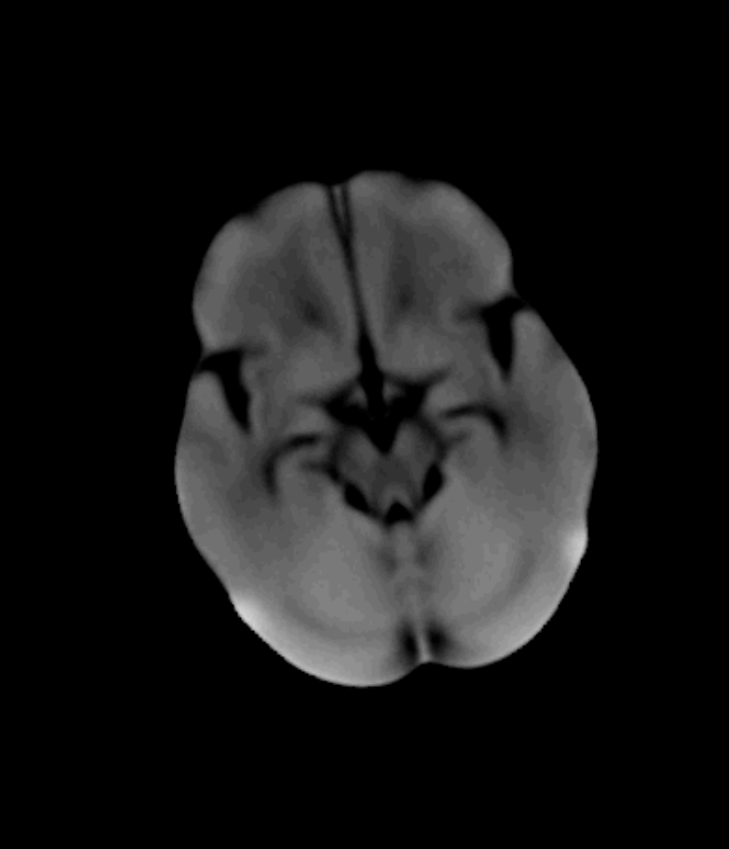

Refer to caption

(a) CTA

(b) Bone Removal Mask (a)

The pipeline we propose receives a CTA image as input, an example of which is shown in Fig. 2(a). Alongside the CTA data, a brain atlas (shown already registered to an example in Fig. 2(c), a mean brain over a patient populations) (Kemmling et al., 2012) together with the corresponding vessel atlas (Forkert et al., 2012) (accordingly transformed, shown in Fig. 2(d)) is given. The latter atlas is a volume representing the existence of voxels belonging to a vessel by means of a probability value, whereby it emphasizes on the arterial branches close to the Circle of Willis. In a first step, all bone structures are removed, as indicated in Fig. 2(a), using a method by Chen et al. (2020) which segments those bone structures in CTA scans. An example is shown in Fig. 2(b) which is the bone segmentation of the slice shown in Fig. 2(a). The CTA volume is not only forwarded to the bone removal but also used to register the brain atlas onto in Fig. 2(b). The non-rigid (elastic) registration is based on Chefd’Hotel et al. (2002)’s method specifically designed to register multi-modal volumes. The resulting deformation field is used to transform the vessel atlas (Forkert et al., 2012) in step Fig. 2(c) into the CTA coordinate system. Tubular structures of the bone-free CTA scan, resulting from Fig. 2(a), are enhanced using the Frangi filter (Frangi et al., 1998) (two scales, σ1=1.00subscript𝜎11.00\sigma_{1}=1.00, σu=1.50subscript𝜎𝑢1.50\sigma_{u}=1.50) exemplarily shown in Fig. 2(e). The filter response is masked in Fig. 2(e) with the vessel atlas, which is binarized with a relative threshold of t1=0.5%subscript𝑡1percent0.5t_{1}=0.5\% (of the maximum value) followed by dilation (with a kernel size in z,y and x of 11, 7 and 7, respectively). Fig. 2(f) shows the result of the vessel masked Frangi response, which is thresholded with t2=4subscript𝑡24t_{2}=4. Values below that threshold are suppressed to zero, values above are kept with the original values. With this step, noise is being reduced which stabilizes the subsequent steps, like the slice-wise circle based Hough transformation in step Fig. 2(f)(canny threshold = 10, accumulator threshold = 1, min distance = 5, min radius = 0, max radius = 5 and accumulator threshold = 1). The goal of the Hough transformation is to identify circle-shaped structures in the given slices, however, as shown in Fig. 2(g) many centerpoints of the detected circles do not match with the preliminary vessel tree segmentation. Hence in the next step, the mask used for the Hough transform is reused again, to mask out in step Fig. 2(g) all centerpoints which do not align with the segmentation. The example shown in Fig. 2(g) originally has 6747 centerpoints in total, reduced to 1375 by the masking, the result of which is shown in Fig. 2(h). The remaining points are used as seed points for region growing in Fig. 2(h). The region growing segments all voxels connected to the seed points, whose intensity differs no more than ±5%plus-or-minuspercent5\pm 5\% from the average intensity of the seed point voxel values. The result is a preliminary segmentation which only includes vessel segments represented in the original vessel atlas. As will be described below, this mask is used for labeling. The result is shown in Fig. 2(i). In order to segment all vessels, especially more distant vessel structures, the segmentation mask of step Fig. 2(h) is transformed into seed points which are used for the final region growing in Fig. 2(h) segmenting every connected voxel with a value in the range of 130 HU to 1500 HU. Its result is the final segmentation, shown in Fig. 2(j). The whole pipeline has been implemented in MeVisLab 3.4, MeVis Medical Solutions AG, Bremen.